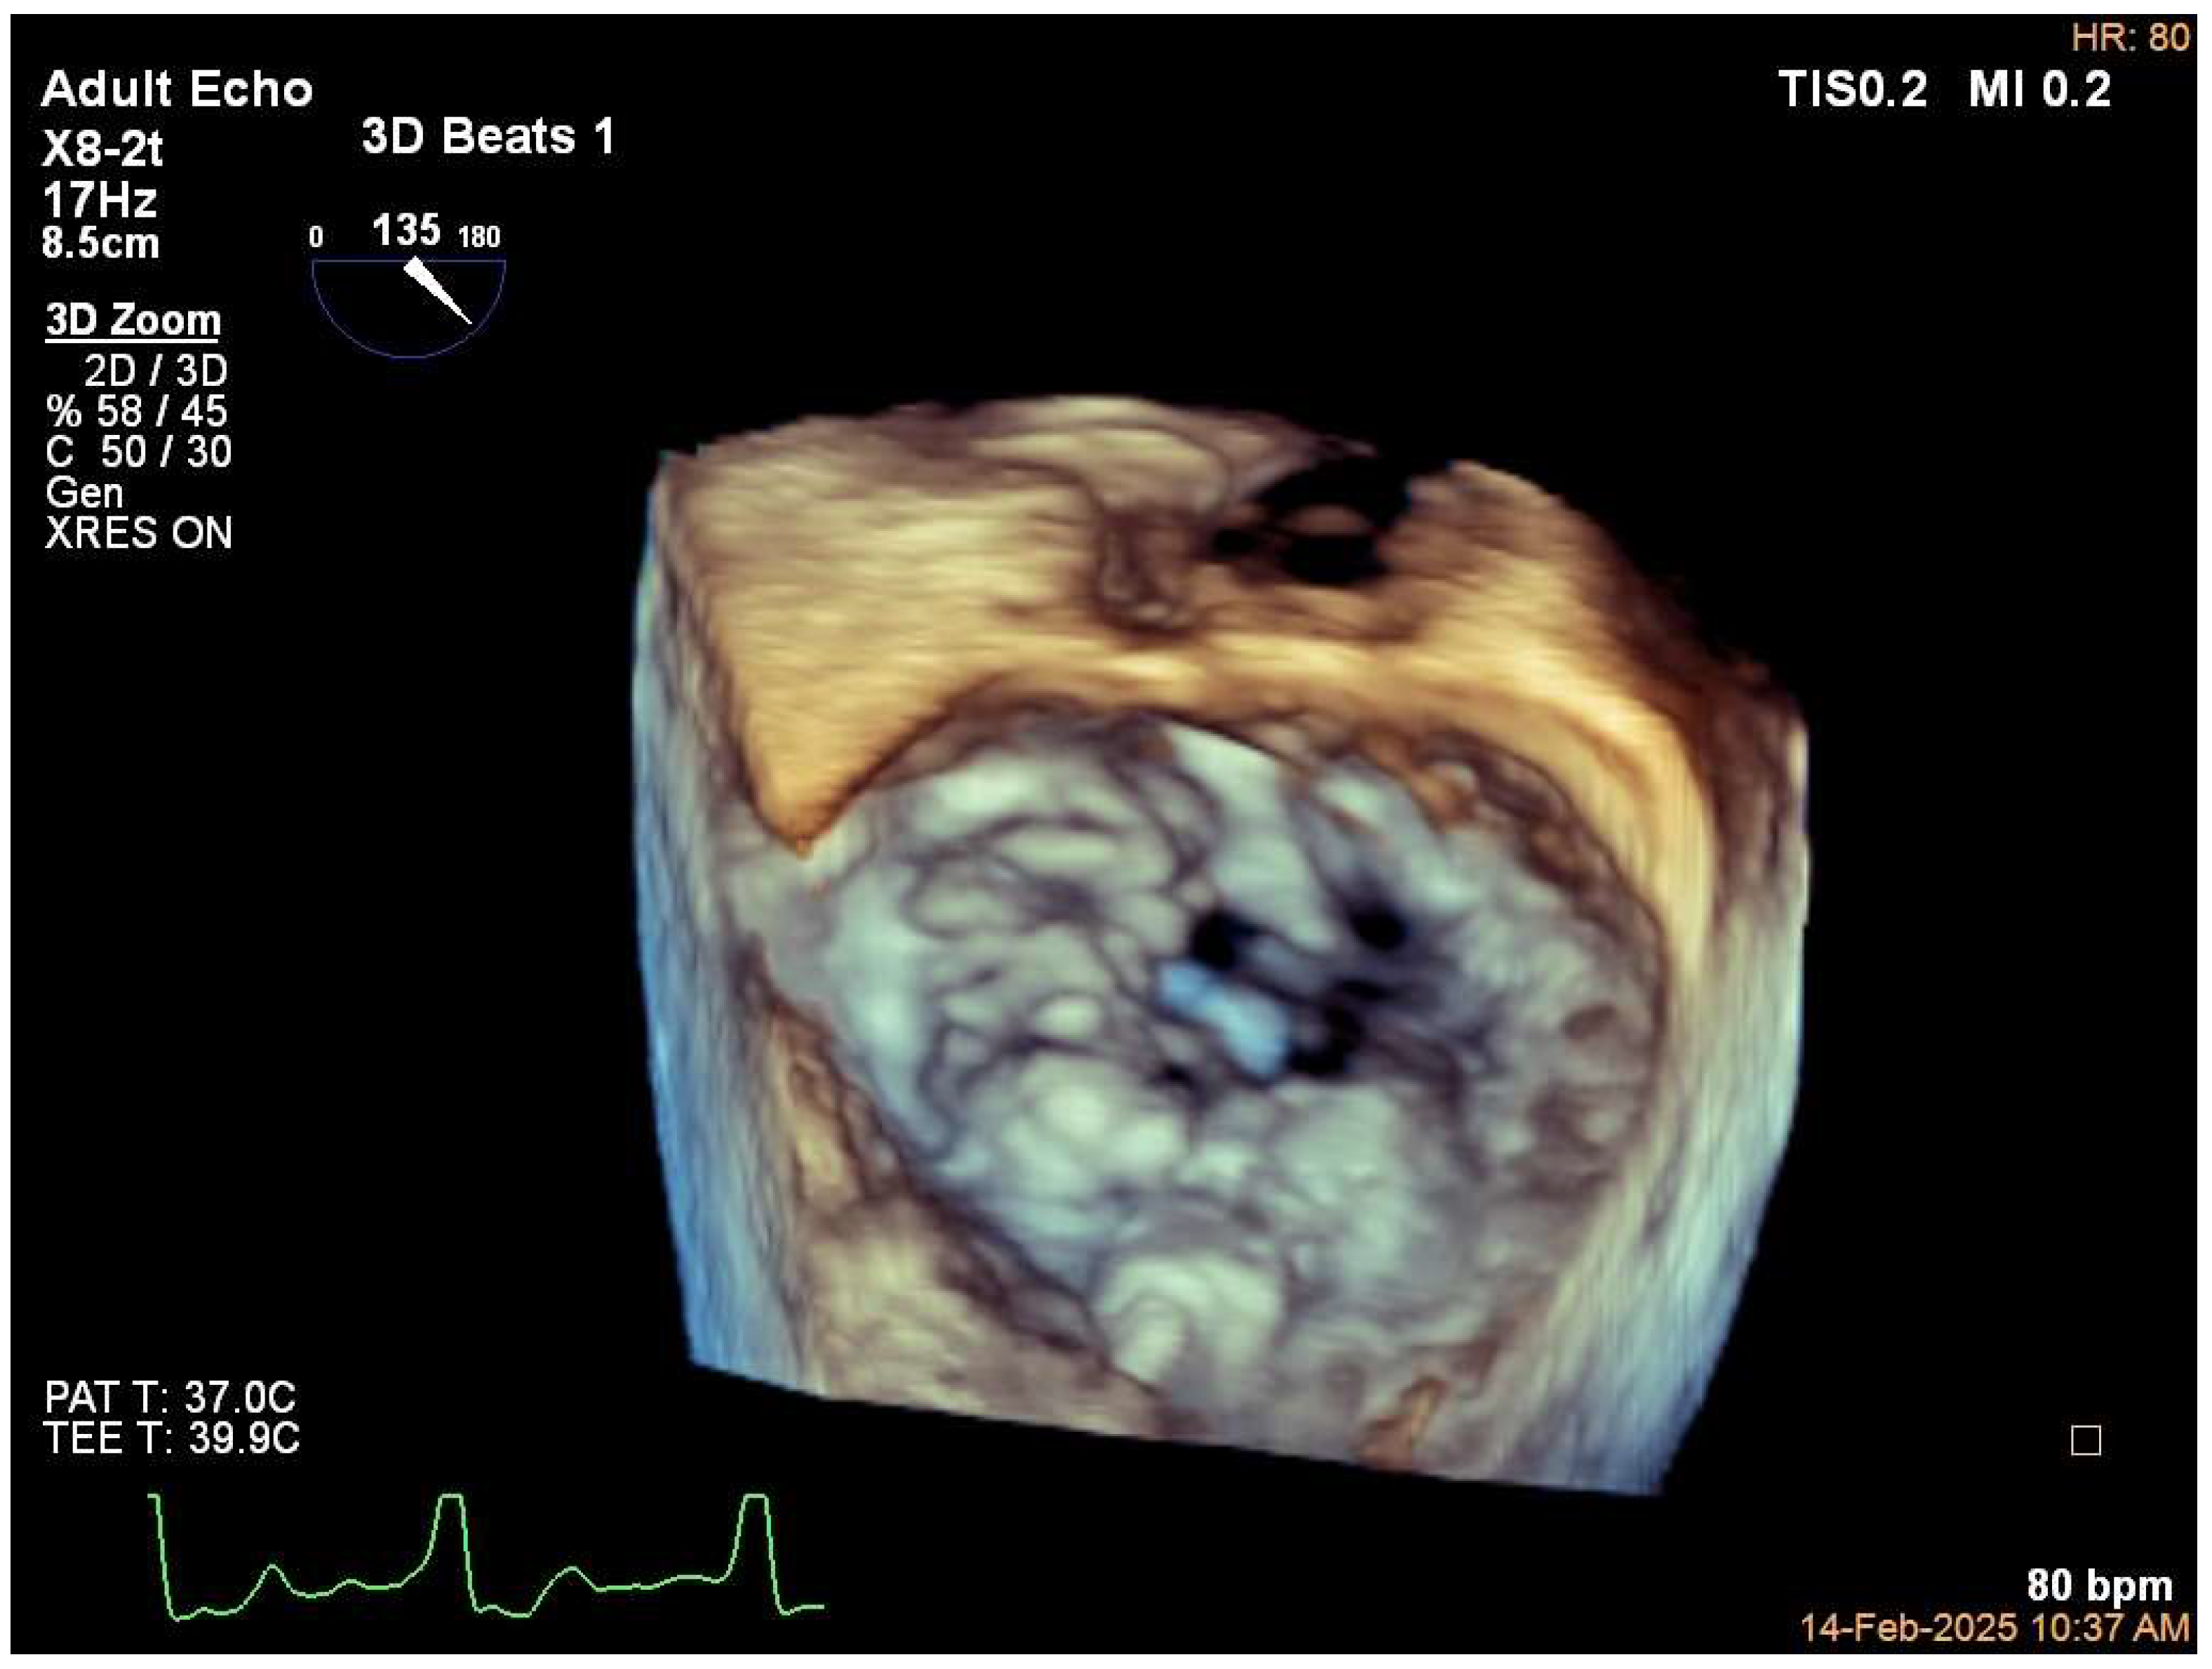

5.1. Case